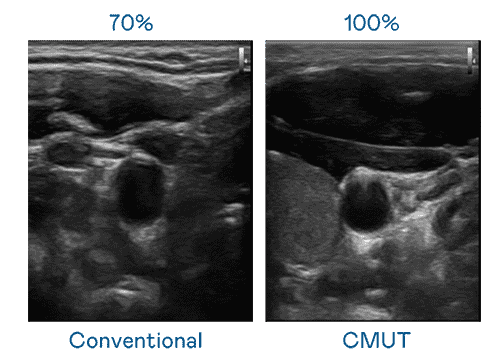

CMUT 技术是一种用电容式微机电元件来产生超音波讯号的技术。。与传统 PZT 压电式技术相比,,CMUT 频宽增加 30%,,,更宽频的超音波讯号让影像解析度大幅提升,,,是实现高影像品质医疗超音波扫描、、、促进精准医疗发展的关键技术。。

大频宽带来超清晰影像

超音波影像的解析度高低,,,首先取决于探头能发出的讯号频宽。。。尊龙集团 CMUT 可提供高清晰的超音波讯号,,,,提供高频宽、、高灵敏度、、影像纹理细节更高的超音波影像,,,协助医护人员缩短影像判读时间及利用精准的医疗影像进行诊断。。